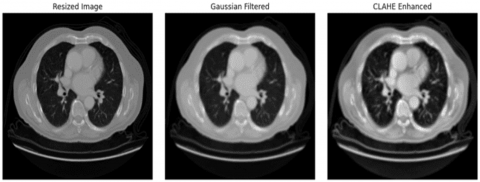

Image preprocessing defines the data preparation phase, where the system converts the raw CT images into an appropriate format for further processing. This stage follows a sequence of processes such as noise filtering, image resizing, and contrast enhancement or background elimination. In the noise filtering step, a Gaussian filter was applied to the images to eliminate the noise or unwanted random variations within each image. The Gaussian filter removes the noise attributes and replaces them with the average value of nearby or surrounding attributes, which is estimated by Gaussian distribution. The mathematical formulation of the Gaussian filter is expressed in Eq. (1):

where, Gs(m, n) represents the Gaussian filter, Cim(m, n) denotes the input CT image, (m, n) indicates the kernel coordinates, and ∂ refers to the standard deviation. Consequently, the filtered images are resized into a common size to boost the dataset consistency. Finally, background removal was done to discard the unwanted regions from the CT images. This process is done using image thresholding. This step helps the system to focus on useful regions in the images. In addition, data augmentation was performed to reduce the risk of overfitting. This step creates new training samples by performing steps like rotation, random translation, scaling, image mixing, etc. Figure 3 displays the preprocessed images.

Figure 3. Preprocessed images